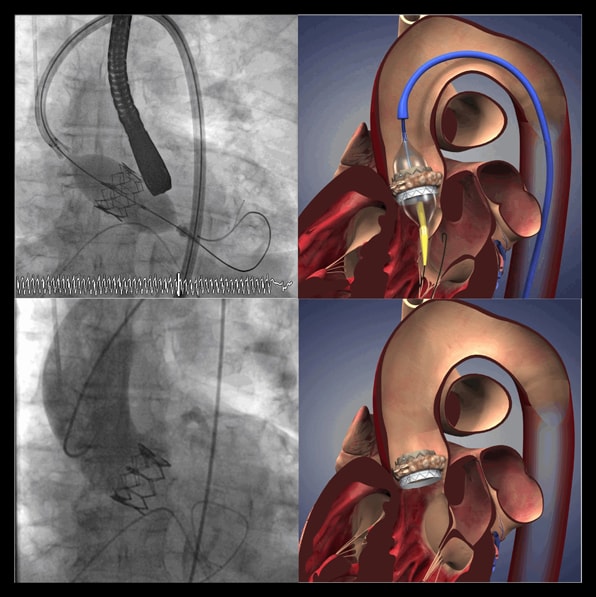

Profesionales del Centro Integral de Enfermedades Cardiovasculares (CIEC) de HM Hospitales encabezados por el Dr. Eulogio García, responsable de su servicio de Hemodinámica Cardiaca, realizaron recientemente dos procedimientos consecutivos de implantación de válvula aórtica por procedimientos percutáneos para tratar a dos pacientes con estenosis aórtica (patología caracterizada por el estrechamiento anormal del orificio de la válvula aórtica del corazón) para los que, tras una sesión multidisciplinar de todos los servicios integrantes del CIEC, se desestimó la cirugía extracorpórea convencional por conllevar un alto riesgo.